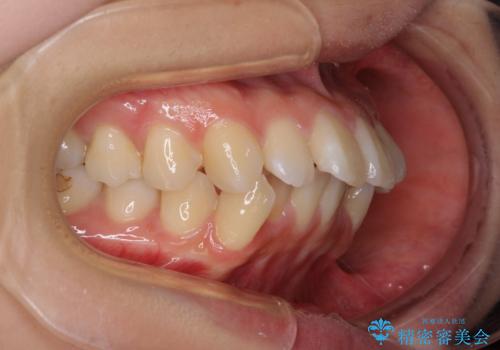

- 前歯のデコボコや口元の突出感、口の閉じにくさを気にして来院された患者様です。

上下左右第一小臼歯4本を抜歯し、ワイヤー装置にてデコボコを解消しながら口元を引っ込めるよう矯正治療を行うこととしました。

抜歯スペースを閉じている過程で、左側の上下犬歯が引っかかってしまい、進捗が停滞しましたが、当初予定の2年~2年半の間で無事に治療を終えることができました。